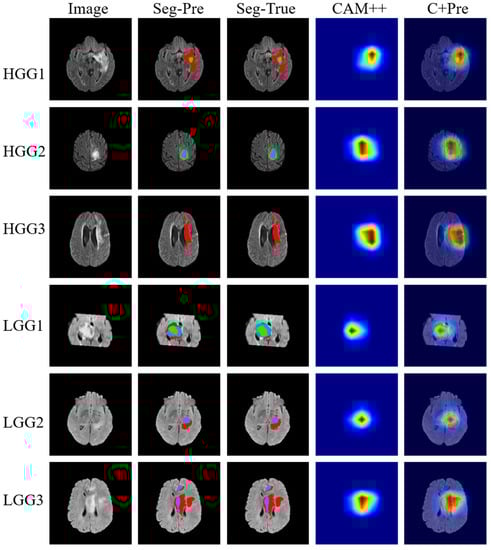

4.3.2. Classification Results

4.3.3. Comparison of Segmentation and Explainability